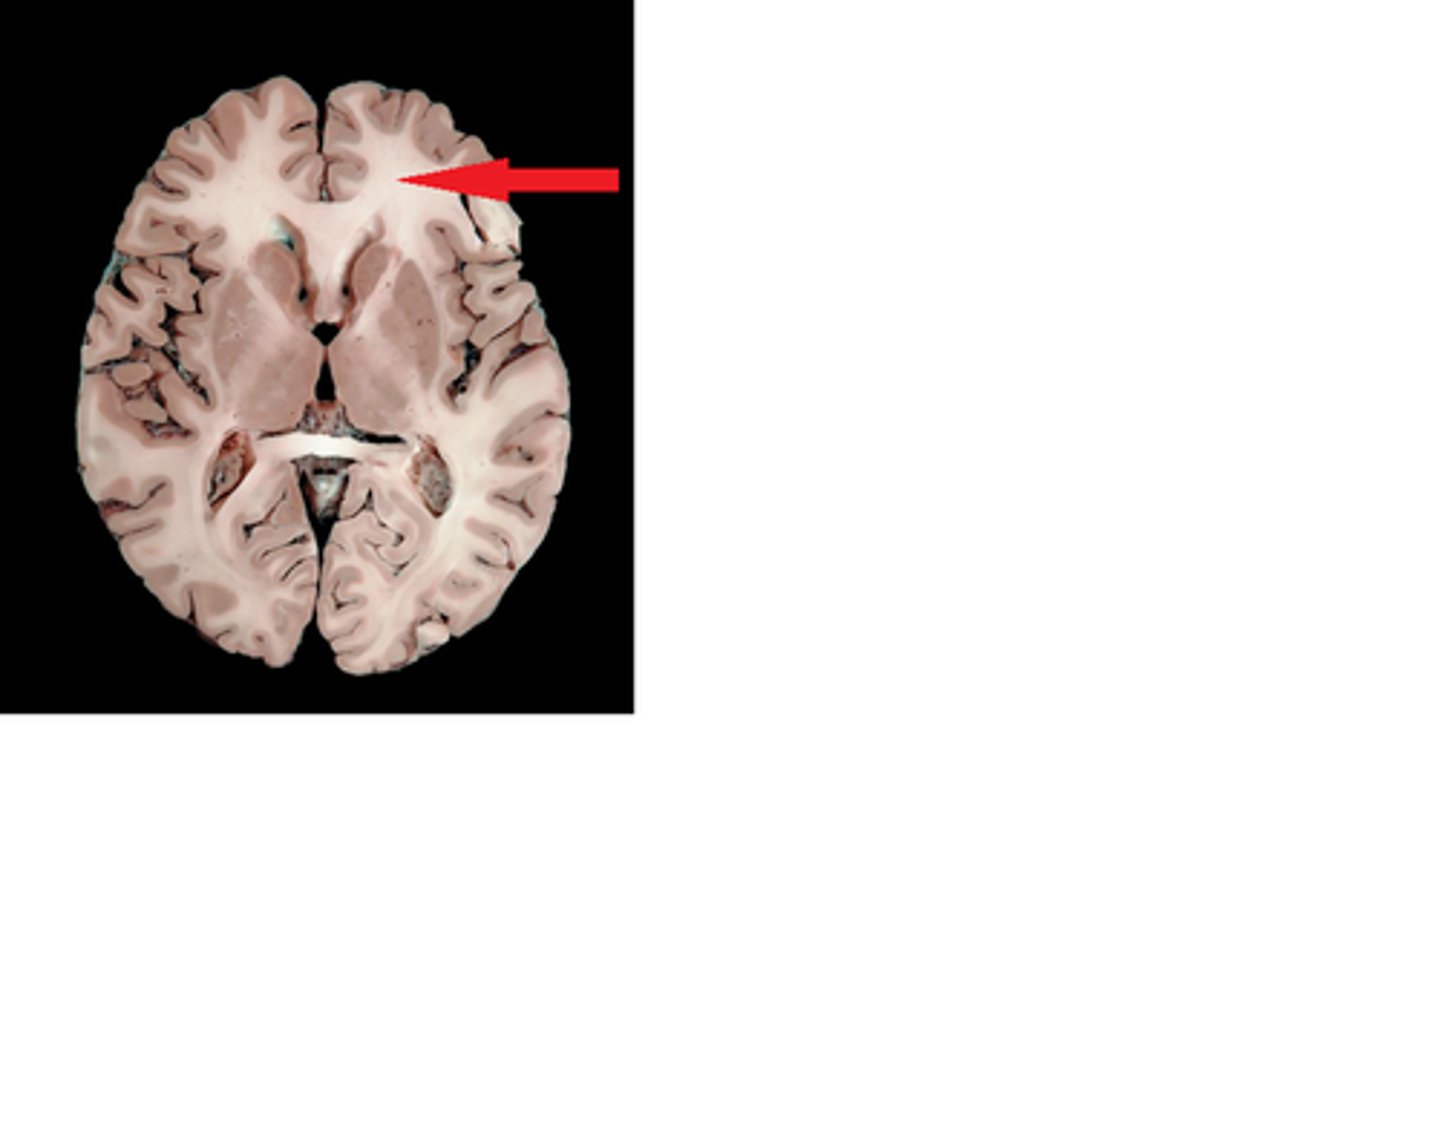

Caudate Nucleus

Globus Pallidus

Putamen

Choroid Plexus